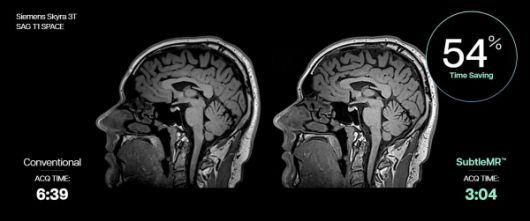

서틀엠알은 지멘스 헬시니어스 3.0T MRI ‘스카이라’(Skyra)의 뇌 시상면 방향 고해상도 3D T1 강조 영상(SAG T1 SPACE) 촬영 소요 시간(ACQ TIME)을 기존 6분 39초에서 3분 4초로 54% 단축했다. |